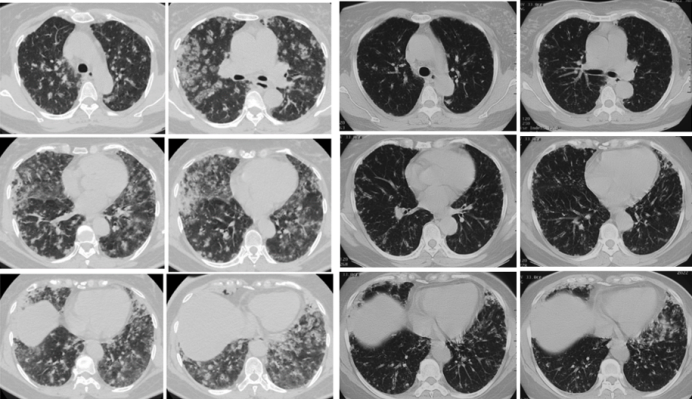

51岁女性患者,发热、咳嗽3天,呼吸困难1天,患者3天前无明显诱因出现发热,Tmax 38°C,伴咳嗽;1天前活动时出现憋气,夜间平卧后咳嗽明显。银屑病病史20余年,主要表现为双上肢及胸腹部皮疹,3个月前开始应用依奇珠单抗共3次。

动脉血气(FiO2 21%):pH 7.44,PaCO2 37 mmHg,PaO2 56 mmHg;血常规WBC 9.37×109/L,NEU% 81.6%,CRP 120 mg/L;肝肾功能及心肌酶无异常,K+ 3.26 mmol/L(↓),Na+ 135.1 mmol/L(↓);D-Dimer 0.33 mg/L。

左舌叶支气管肺泡灌洗100 ml,回收45 ml(淡黄色);左B9+10冷冻肺活检取4块组织标本。BALF白细胞分类:巨噬细胞14%,中性粒细胞3%,淋巴细胞75%,嗜酸细胞8%;BALF NGS提示结核分枝杆菌复合群(序列数14),其他病原学均为阴性。送检肺组织,支气管壁内淋巴细胞、浆细胞及嗜酸性粒细胞等多型炎细胞浸润,间质纤维增生,局灶肺泡上皮增生,肺泡腔内纤维素蛋白样物沉积。考虑炎症性病变,未见肉芽肿,抗酸染色阴性。组织mNGS(-)

结合患者病史及查阅相关文献,最终考虑诊断IL-17诱导药物导致的间质性肺炎。给予甲泼尼龙40 mg qd联合二联抗结核治疗后,肺部病变较前明显改善(图2)

图片

2  患者治疗前后胸部CT比较